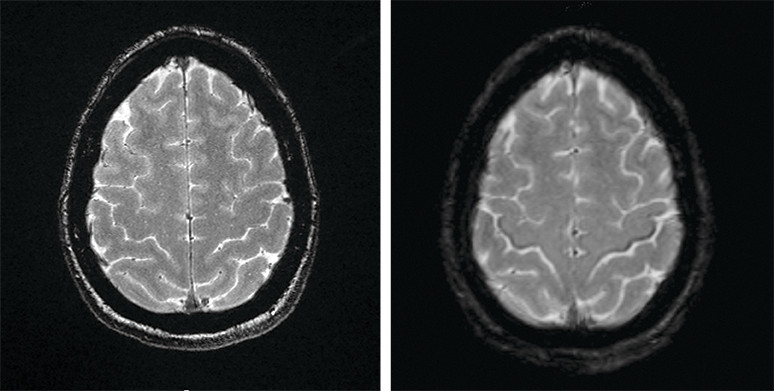

Susceptibilitetsvektede MR-bilder (SWI-magnitude) av hjernen (bildet til høyre) viser lavsignal forenlig med jernavleiring i bakre deler av gyrus precentralis tilsvarende motorisk korteks på begge sider hos en pasient i 50-årene med amyotrofisk lateral sklerose (ALS) (1, 2). Det såkalte svart bånd-tegnet (motor band sign / black ribbon sign) synes ikke på MR-bildene tatt ett år tidligere (bildet til venstre).

Pasienten debuterte med bulbære symptomer i form av svelg- og talevansker. Hun utviklet et halvt år før MR-bildene ble tatt et stormende klinisk bilde av uttalt tetraspastisitet, som responderte godt på peroral behandling med baklofen.

Ved utredning av mistenkt amyotrofisk lateral sklerose har MR-undersøkelse til nå blitt brukt differensialdiagnostisk med tanke på andre årsaker til øvre motornevrontegn (for eksempel cervikal myelopati og cerebrovaskulære forandringer). Kasuistikken illustrerer at magnetisk resonanstomografi kan vise spesifikke funn ved amyotrofisk lateral sklerose, som jernavleiring i gyrus precentralis. I en prospektiv studie fra Mexico hadde 92 % av 38 ALS-pasienter «svart bånd-tegn» på tre tesla-MR-undersøkelser (1). Ved Oslo universitetssykehus har vi fra 2020 begynt å gjøre MR med SWI-sekvenser rutinemessig ved utredning av amyotrofisk lateral sklerose.